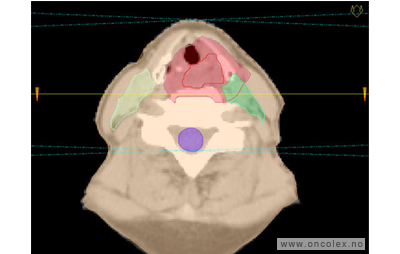

Skisse over hvordan strålefeltet planlegges:

Illustrasjon for målvolum

• GTV (Gross Tumor Volume): Identifisert tumor.

• CTV (Clinical Target Volume) GTV + omkringliggende vev hvor det kan væremikroskopisk spredning.

• ITV (Internal Target Volume): CTV + en indre margin som tar hensyn tilindre bevegelser og endringer av CTV.

• PTV (Planning Target Volume): Innstillingsmargin som inneholder ITV og samtidig tar hensyn til antatte pasientbevegelser, samt variasjoner i pasientopplegging og feltinnstillinger.

• Feltgrense. Tegnes som oftest på kroppen.

ICRU (International Commission on Radiation Units and Measurements)